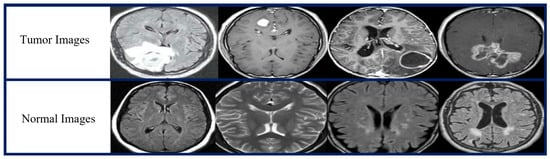

| Tumor Type | No of MRI Images | MRI Views |

|---|---|---|

| Tumor | 1500 | Axial, coronal, sagittal |

| Normal | 1500 | |

| Total number of images | 3000 |